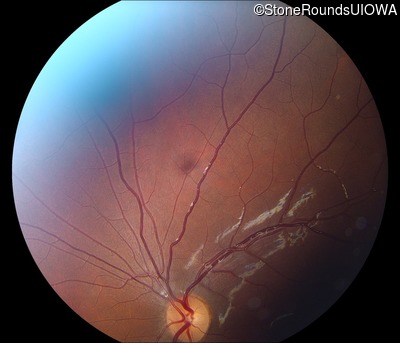

Fundus Photography - Right -

20/100 -2

Fundus Photography - Left -

20/100

Visit at age: 11 years

AR Stargardt Disease (IIA)

AR Stargardt Disease

ABCA4

Gly1961Glu GGA>GAA, Arg212Cys CGC>TGC